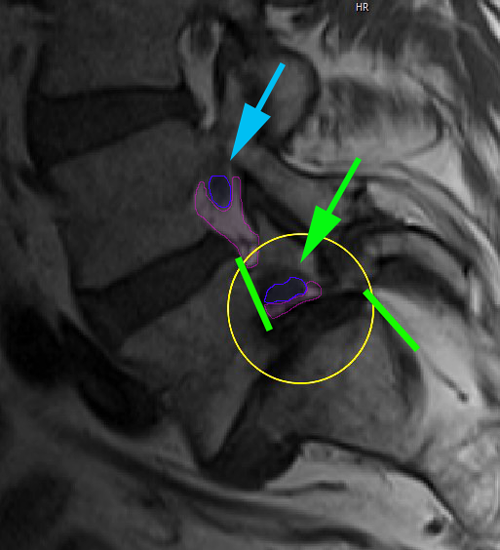

Σπονδυλολίσθηση 3ου βαθμού Ο5-Ι1, ισθμική. Η προσθιολίσθηση του Ο5 σπονδύλου επί του Ι1 απεικονίζεται με την απόσταση ανάμεσα στα οπίσθια τμήματα του σώματος των σπονδύλων (πράσινες γραμμές). Το νευρικό τρήμα παρουσιάζει σημαντική στένωση στο επίπεδο της σπονδυλολίσθησης (κίτρινος κύκλος, τρήμα με φούξια, νεύρο με μπλέ) σε σχέση με το άνωθεν αυτού φυσιολογικό (κυανό βέλος). |